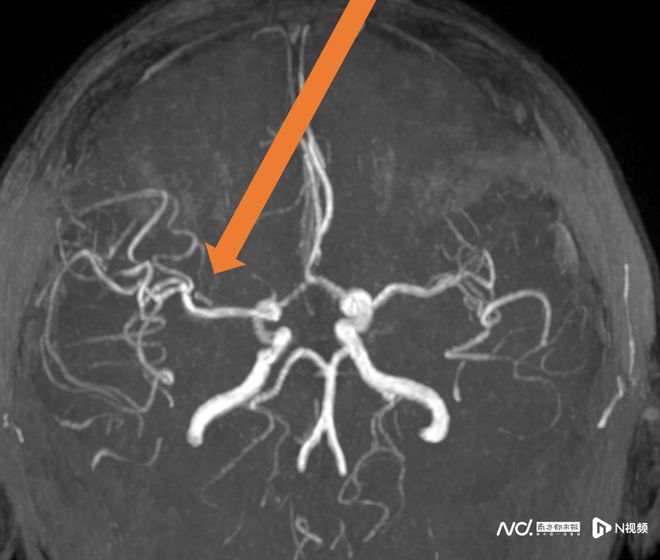

57歲的王阿姨患有風心病,一天吃飯時突然言語不清、左側肢體無力無法站起。家人立即撥打120,經卒中綠色通道確診為右大腦中動脈閉塞,隨即進行靜脈溶栓。